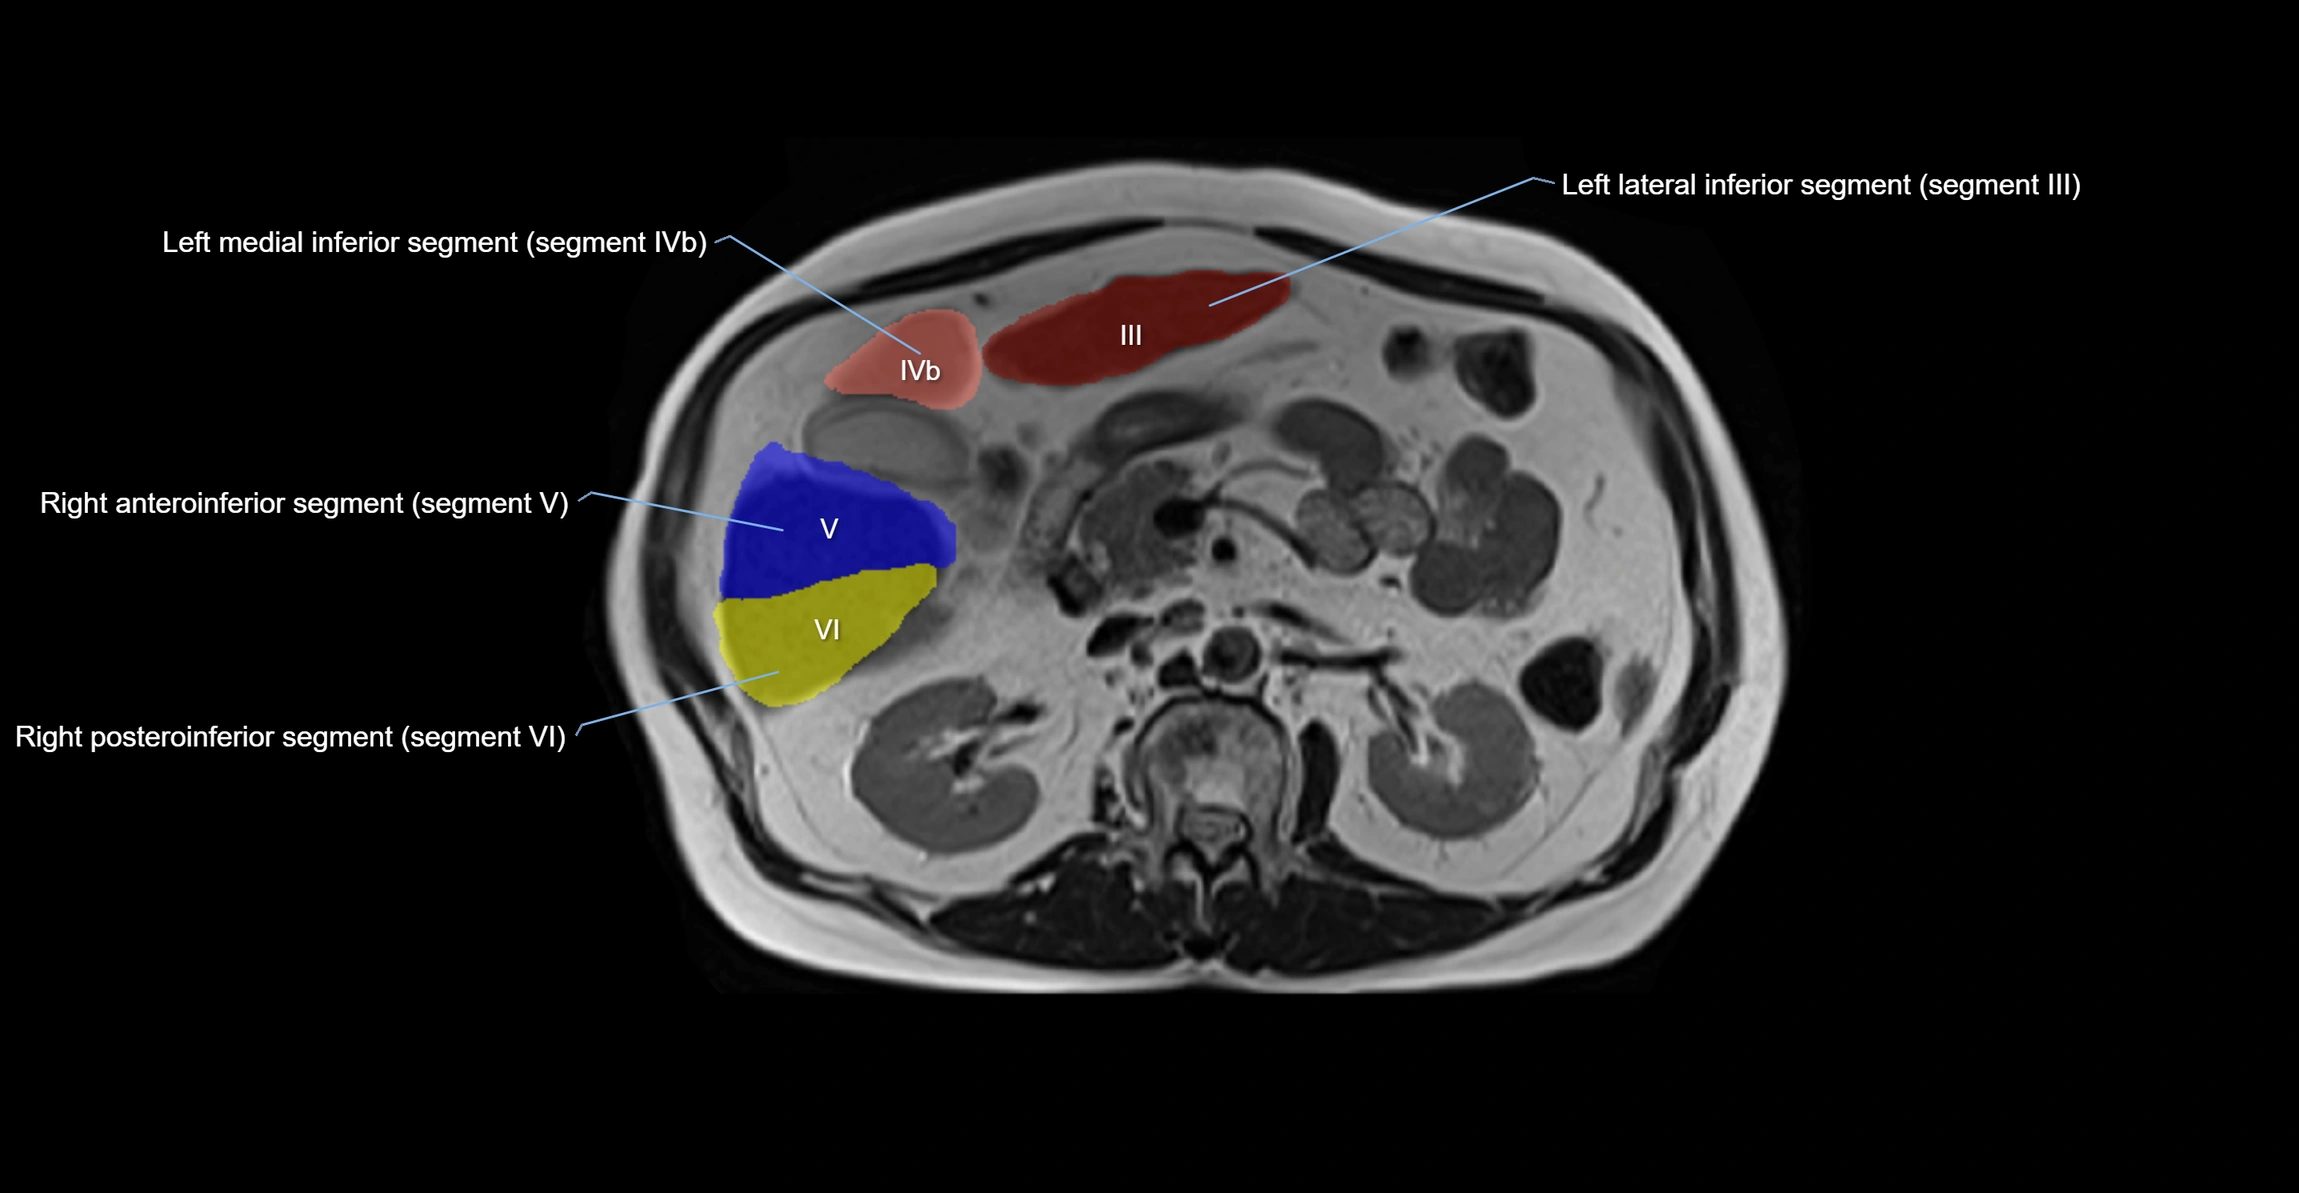

The caudate lobe of the liver is a distinct anatomical subdivision of the liver, designated as segment I in Couinaud’s classification. It lies on the posterior surface of the liver, between the fissure for the ligamentum venosum (left boundary) and the groove for the inferior vena cava (IVC) (right boundary). Superiorly, it is related to the posterior liver surface, and inferiorly it is separated from the left lobe by the porta hepatis.

The caudate lobe is unique because it receives dual portal venous and arterial inflow from both the right and left portal veins and hepatic arteries. It also has independent venous drainage directly into the IVC via multiple small hepatic veins, unlike other lobes that drain through the three main hepatic veins.

MRI image

image